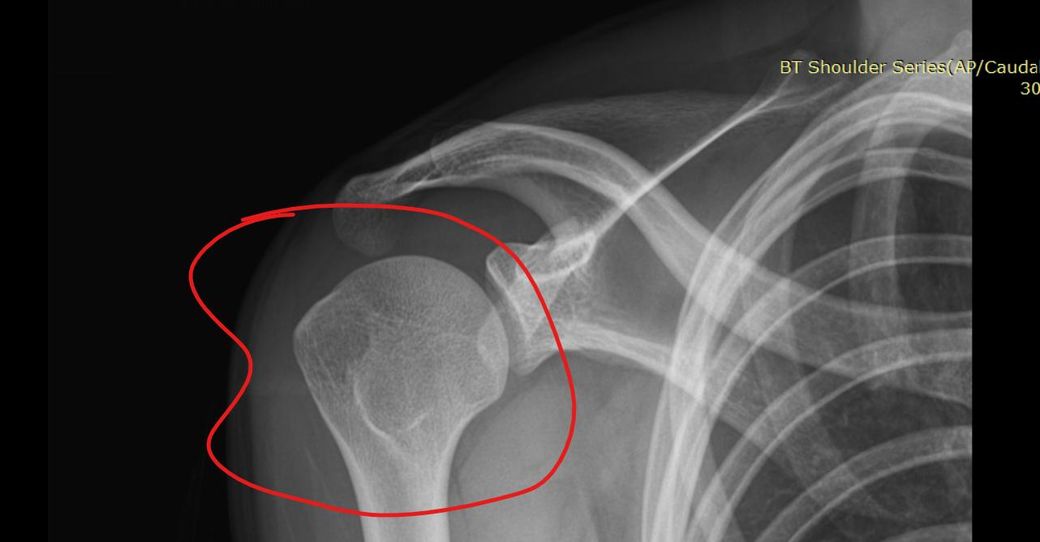

어깨 골수부종인가요 질문합니다 부탁드려요

어깨 골수부종인가요 ? 뼈멍인가요 미세골절인가요 사고나고 뼈에 심하게 멍들었다고 했긴했습니다 전 잘모르겠어서 질문 해봅니다

사진만으로 단정은 어렵지만, 표시된 소견은 보통 “골수부종(=뼈멍)”에 가장 가깝습니다.

골수부종은 “강한 충격 후 뼈 안에 물이 찬 상태“로, 미세골절과 영상상 겹쳐 보일 수 있습니다.

“미세골절”은 골수부종보다 통증이 오래.강하고 체중부하/사용 시 악화되는 경우가 많습니다.

치료는 대부분 “안정.사용.제한.소염치료”이며, 정확한 판정은 판독지와 진찰이 필요합니다.

뼈 내부에 멍처럼 부종이 발생한 골수부종으로 생각되는데요, 자세한 소견은 MRI를 촬영하신 이후 받으신 판독지나 진단서와 같은 서류 혹은 주치의에게 확인을 해보시는 것이 정확하겠습니다.